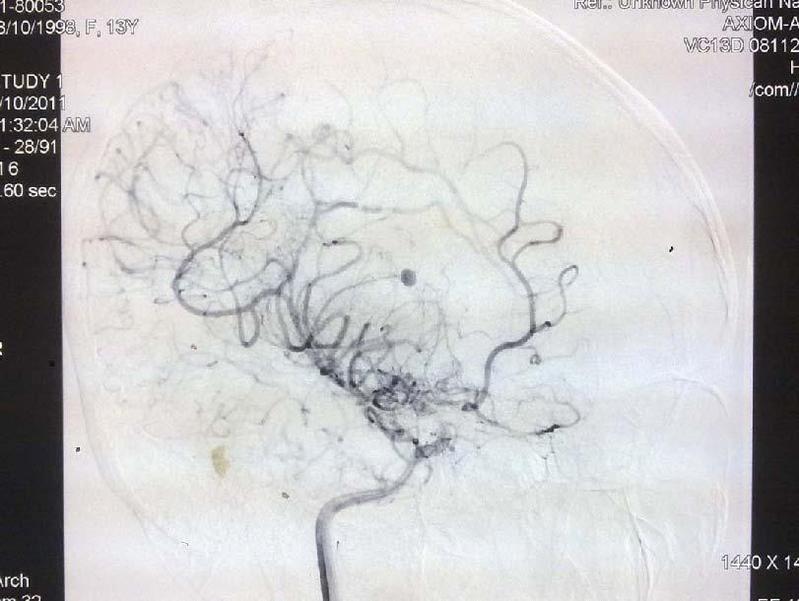

典型病例4:动静脉畸形